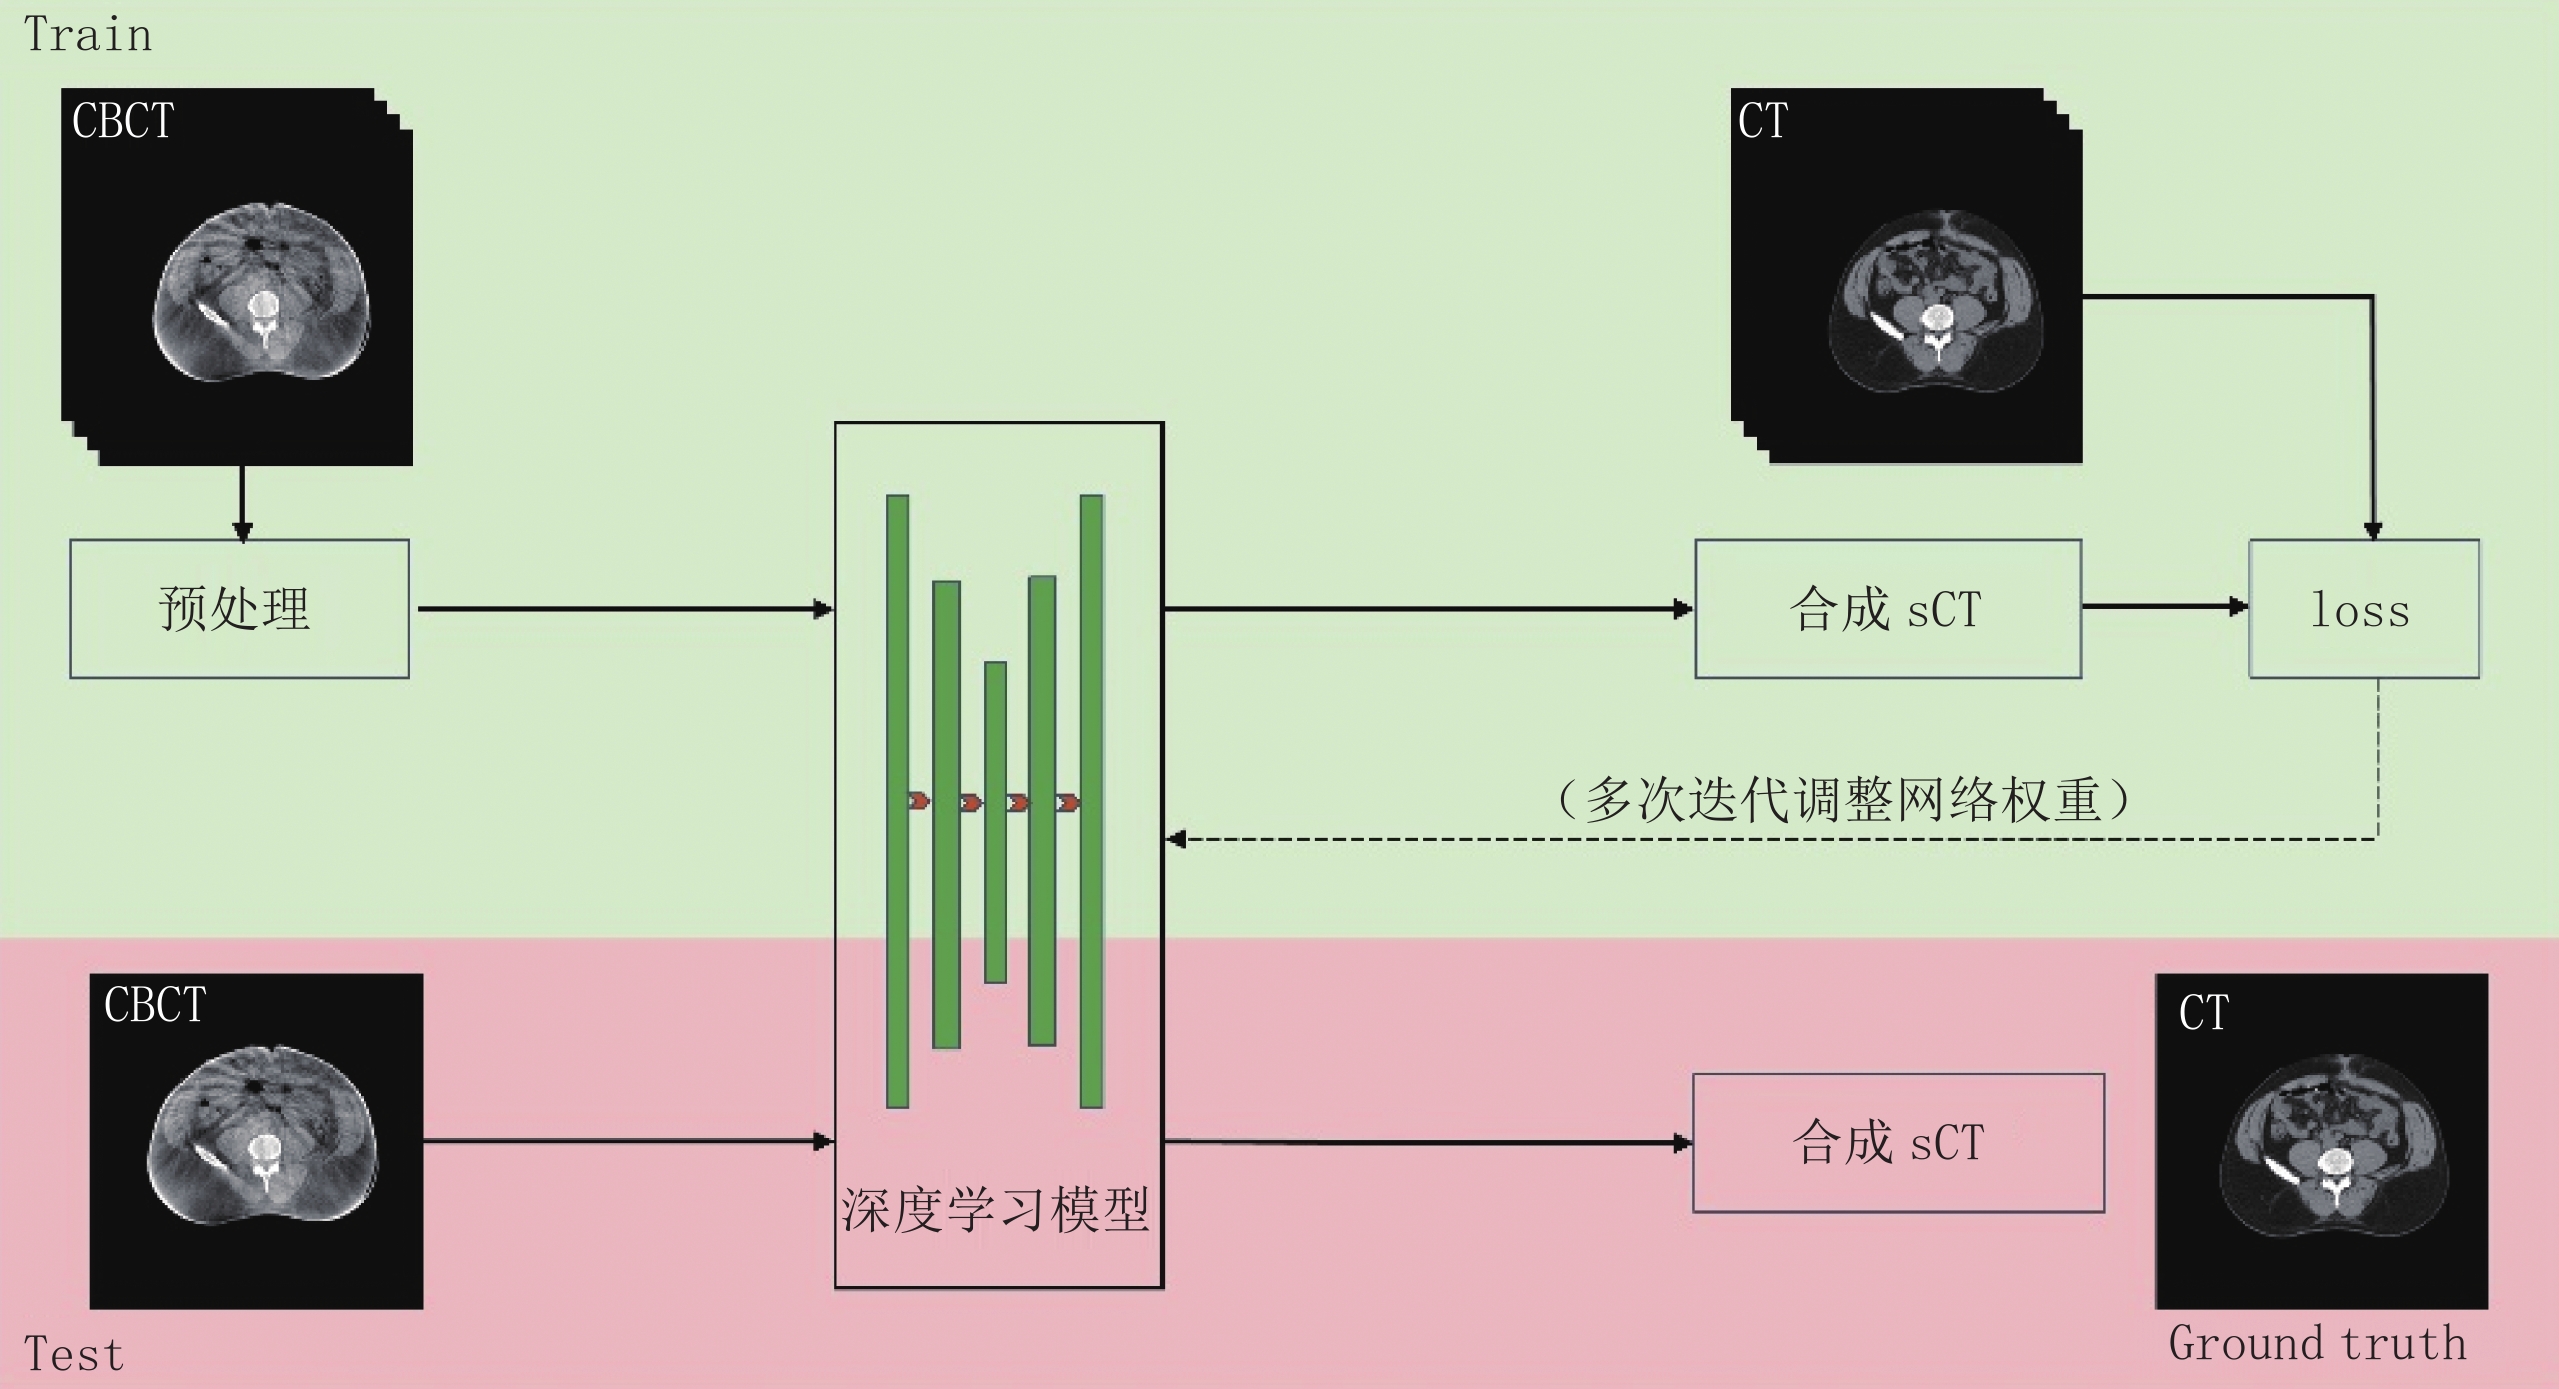

$ {I_p} $ 与散射点扩展函数$ {h_{{\rm{PSF}}}} $ 进行卷积,再与权重函数$ {W_{(T)}} $ 相乘得到散射强度${I_s} = {W_{(T)}} \cdot {I_p} * {h_{{\rm{PSF}}}}$ [16],并通过实验来获得改进的散射点扩展函数中的相关系数以及权重函数,该方法非常依赖所设置的实验条件,不能提供所有可能的CT场景且完全正确的散射估计[16-18]。MC方法是随着计算机计算能力的发展而出现的以概率统计理论为指导的一类数值计算方法,该方法能够精确地模拟粒子运输,被认为是锥形束CT散射伪影校正的金标准[19],但真实模拟实际的物理过程,导致其计算量大,模拟速度缓慢[20];有许多学者也研究了MC方法的加速策略,如使用GPU加速计算过程,使用低光子数的MC仿真[21],使用深度学习方法得到低光子数到高光子数的图像映射[22],减少对未到达探测器粒子的追踪[23];使用MC和卷积核混合方法[24]等。玻尔兹曼运输方程散射估计方法首先将CT投影过程划分为3个步骤:射线源到扫描对象的光子追踪、光子在扫描对象内的吸收或散射、扫描对象中所有体素到每个探测器像素的散射通量追踪,然后使用线性玻尔兹曼输运方程确定性求解器计算每个步骤中的光子和散射光子的路径,并得到探测器处的散射光子分布,有研究表明该方法可以在临床可接受的时间内获得可靠的校正精度,是一种很有潜力的MC替代方法[25-26]。软硬件混合校正的方法包括:散射校正板校正方法、初级射线调制校正方法等。散射校正板将一块嵌有规则排列的柱状金属的有机玻璃板,置于被测物体和探测器之间[27],得到被金属阻挡位置上的散射情况,拟合得到整个散射分布,其硬件结构如图2(a)所示,校正原理如图2(c)所示,该方法需要被照射对象接受两次照射,增加患者的辐射剂量[28]。初级射线调制校正方法[29-30]将一片均匀布满突起的铝板或铜板,置于射线源和被测物体之间,形成不同的空间衰减,利用散射线的低频特性,使用高通滤波器对投影滤波,扣除散射线,得到校正后的图像[31],其硬件结构如图2(b)所示,校正原理如图2(d)所示。还有学者提出一种时域初级射线调制校正方法,使用可移动的初级射线调制器来去除伪影[32]。

近年来,随着计算机计算能力的提高,深度学习已经发展出许多应用,包括医学图像处理、医学图像分割、医学图像配准、医学图像分类、目标检测等[33]。一些学者也提出使用深度学习方法去除医用CBCT图像伪影,提高图像质量。2018年,Kida等[34]称首次开发出一种用于改善 CBCT图像质量的深度卷积神经网络的方法。此前2017年一篇会议论文[35]中也提出使用深度学习方法进行能谱CT图像的散射校正,该方法校正伪影的流程图如图3所示,首先使用含散射伪影的CBCT图像做深度学习网络模型训练的输入,不含散射伪影的CT图像做网络模型训练的标签来指导网络模型训练的过程,然后使用训练好的模型处理CBCT散射伪影图像,可以很好地解决散射伪影的问题并提高图像质量。